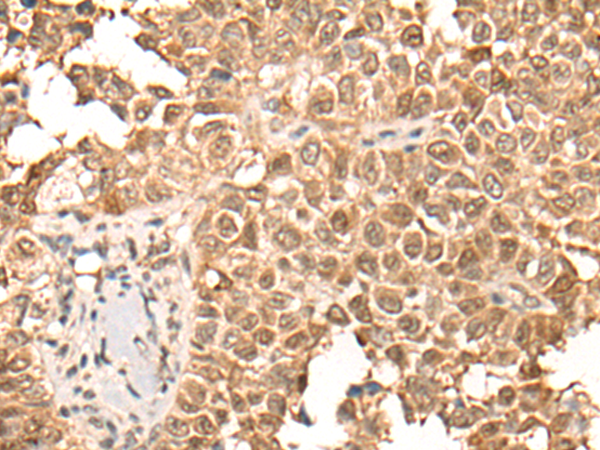

IHC positive control: |

Human ovarian cancer and human thyroid cancer |

IHC Recommend dilution: |

25-100 |